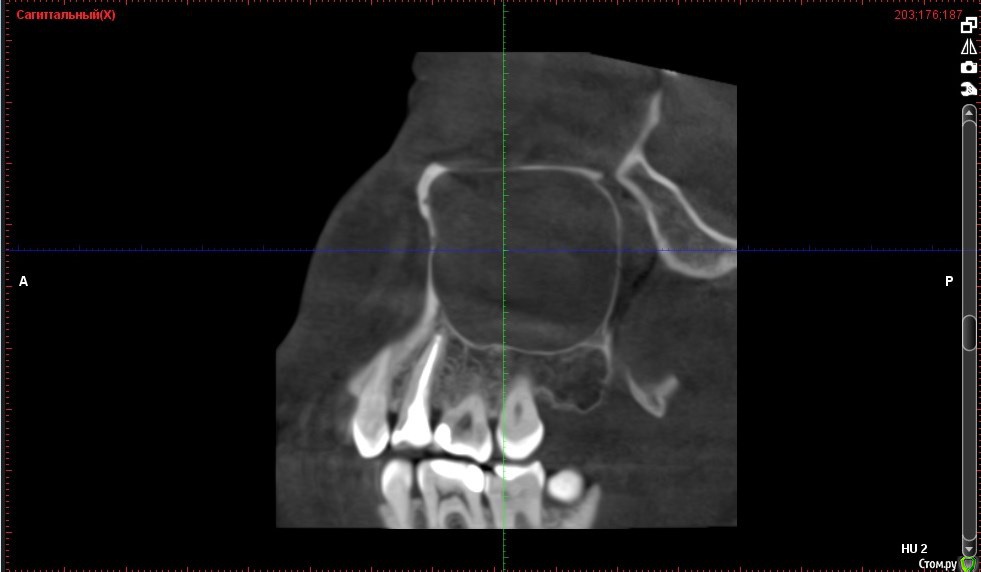

Verasss Опубликовано 8 октября, 2016 Автор Поделиться Опубликовано 8 октября, 2016 КТ от 08.09. Извините, что в таком виде, надо менять ОЗУ. Ссылка на комментарий

DmitrySH Опубликовано 8 октября, 2016 Поделиться Опубликовано 8 октября, 2016 В таком виде КТ малоинформативно. Но гайморита нет. Ссылка на комментарий

Verasss Опубликовано 28 октября, 2016 Автор Поделиться Опубликовано 28 октября, 2016 Добрый вечер! Ещё раз попытаюсь прикрепить скриншоты КТ от сентября. Если качество совсем не устраивает, подскажите, пожалуйста, какие сделать снимки?К сожалению, программа не позволяет вывести снимки на полный экран и заскриншотить в более хорошем качестве. Ссылка на комментарий

Verasss Опубликовано 28 октября, 2016 Автор Поделиться Опубликовано 28 октября, 2016 еще снимки Ссылка на комментарий